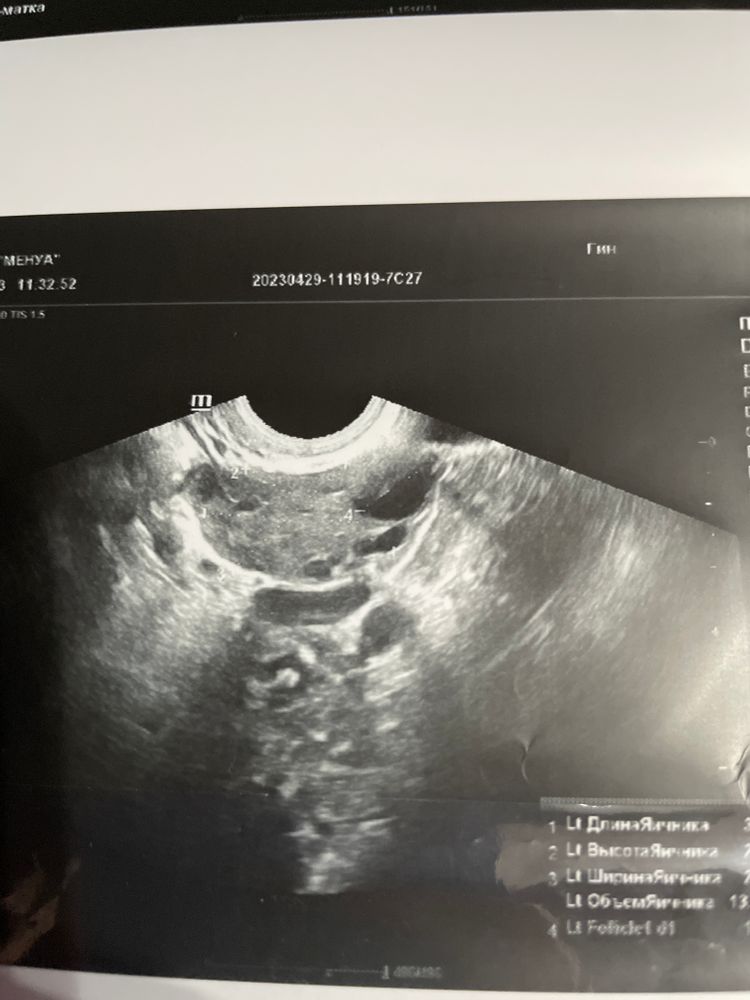

Девочки подскажите ,больше на целый фолликул или жт похоже ?

но и своя овуляция была всегда ) вопрос именно в этом цикле что-то непонятное по заключениям узи